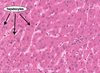

Hepatocytes constitute 80% of the liver cell population and can regenerate.

Describe 6 other unique features of hepatocytes

- Numerous mitochondria

- Numerous peroxisomes (full of oxidising agents)

- Numerous free ribosomes

- Numerous rough and smooth ER

- Numerous Golgi complexes

- Glycogen deposits

What are Kupffer cells and what do they do?

- Kupffer cells are monocyte derived specialist macrophages that form part of the lining of the sinusoids.

- They patrol the sinusoids, recycling old red blood cells and ingesting pathogens

What is a sinusoid and what is unique about its structure?

- A sinusoid is an irregular tubular space for the passage of blood in the liver, spleen and bone marrow

- Its endothelium is perforated with large holes, allowing Kupffer cells to migrate into liver tissue at sites of inflammation and damage

What are stellate cells?

Stellate cells are liver cells which are full of cytoplasmic vacuoles containing Vitamin A